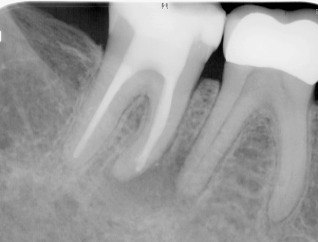

2. What Condition can be seen in this X ray regarding the tooth # 4.4.?